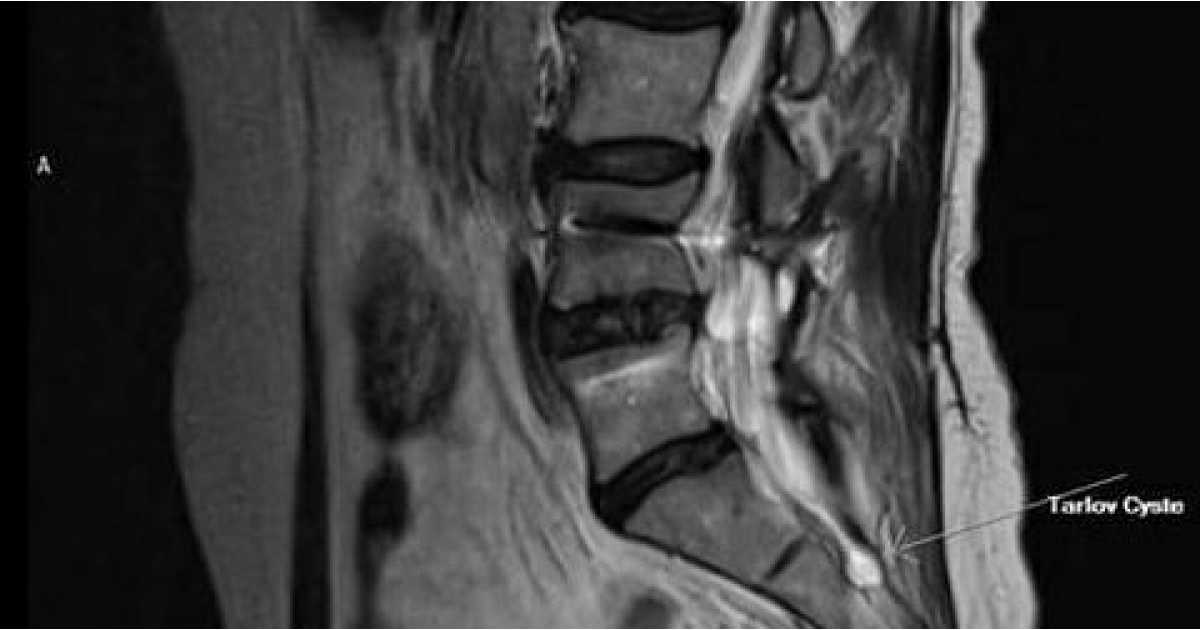

On the scan there was also shown a Cyst in the S2 bone wich has been damaged by the accident smash and is causing pressure on the nerve, wich is the explanation I’m having pain on my tailbone while sitting. Unfortunatly the neurosurgeon in Istanbull didn’t have the know-how about Tarlov cysts and it would have been also too much to do this surgery at the same time as the Spinal Fusion because of the distance between L4/L5 and S2.

While I was recovering from the Spinal Fusion surgery I was looking on the internet for more information about Tarlov Cysts. I found out there are so few doctors that will confirm that those cysts can be sympthomatic. There are only a few who do confirm the symptoms and there even was one neurosurgeon who developed a way to do surgery on them, Dr’Frank Feigenbaum, an American who opened a hospital in Cypruss for European people. I had send him my MRI’s and got a personal phonecall from him in wich he confirmed my Tarlov Cyst is causing the problems and pain. He got me a treatment plan and a bill and I send this to my insurancecompany for funding.